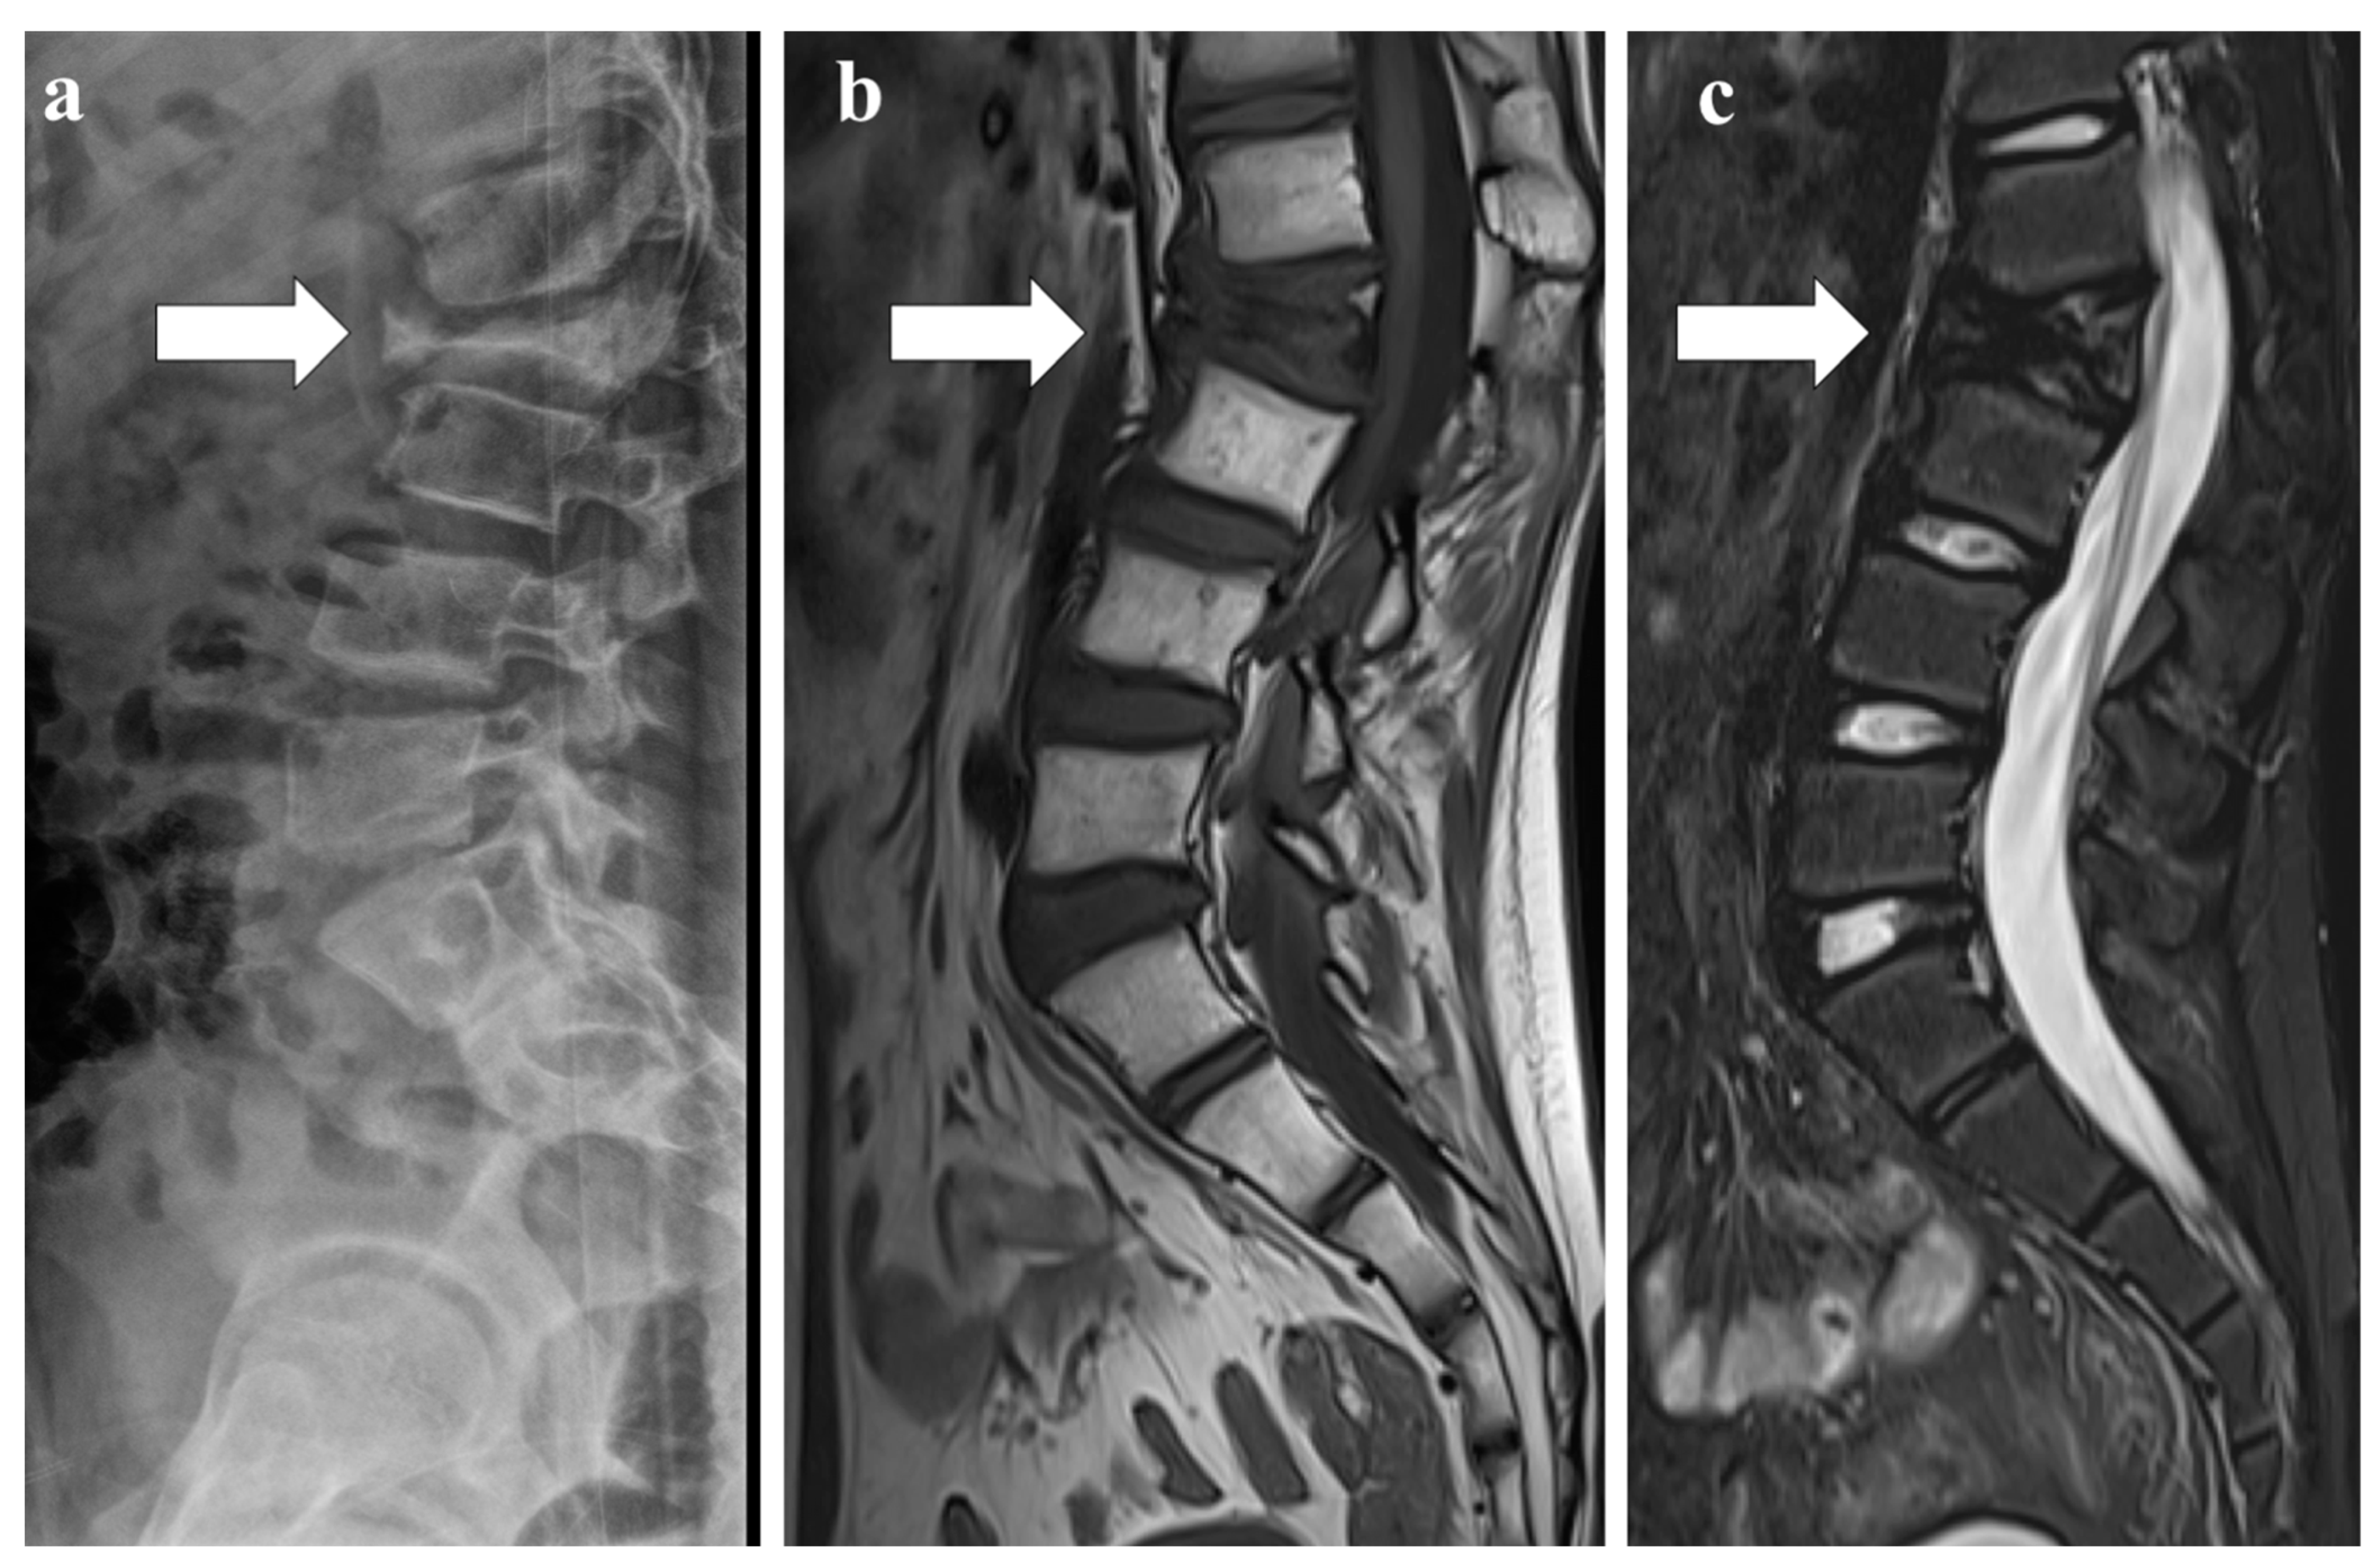

- Sureka, J.; Samuel, S.; Keshava, S.; Venkatesh, K.; Sundararaj, G. MRI in patients with tuberculous spondylitis presenting as vertebra plana: A retrospective analysis and review of literature. Clin. Radiol. 2013, 68, e36–e42. [Google Scholar] [CrossRef]